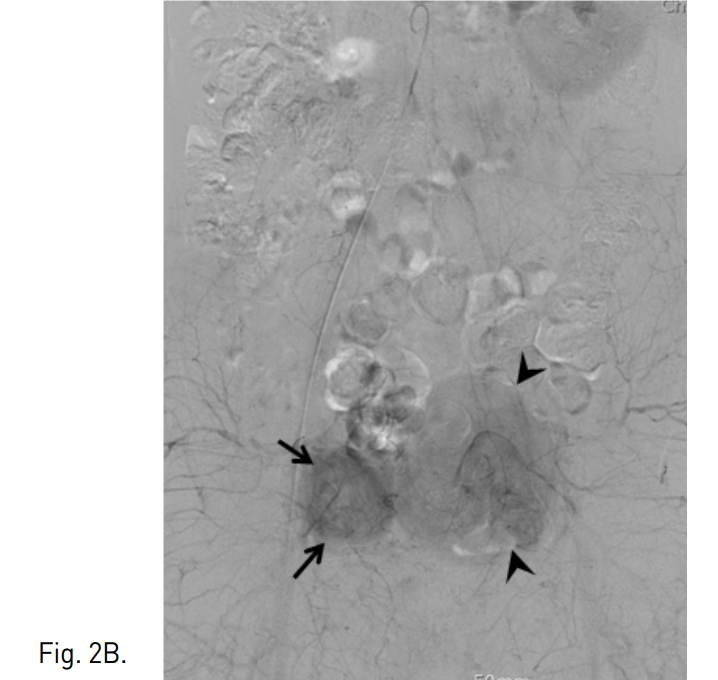

MR영상에서 두 개의 분리된 완전한 자궁과 자궁경관을 가지는 중복자궁(uterine didelphys) 소견을 보였다. 좌측 자궁에 국소형 자궁선근증이 있었고, 우측자궁은 정상 소견이었다(Fig. 1).

Fig. 1. A 38-year-old woman with uterine didelphys.

T2 weighted coronal MR image shows two separated uteruses and focal adenomyosis (arrows) in left-sided uterus.